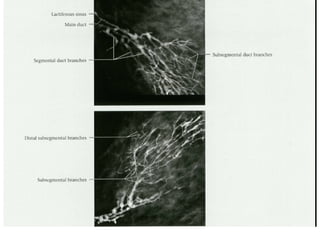

LEFT: Lobular calcifications: punctate, round or 'milk of

calcium‘

RIGHT: Intraductal calcifications: pleomorph and form

casts in a linear or branching distribution.